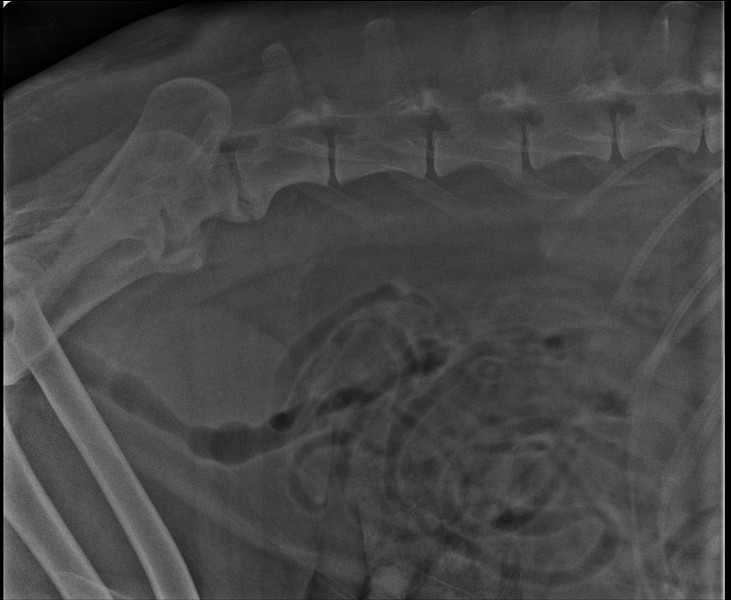

Здравстуйте. Отсутствие опороспособности на тазовые конечности может быть по разным причинам, это могут быть проблемы обусловленные ортопедическими либо неврологическими заболеваниями. Для выявления характера поражения необходимо проводить ортопедический и неврологический осмотр пациента. К сожалению вы не предоставили результаты осмотра. Каковы предварительные диагнозы по результатам исследования? Результаты пересланных вами МРТисследований не выявили каких- либо изменений, возможно, что проблема локализована не в области шеи и головного мозга, либо проблема не обусловлена компрессионными факторами. На рентгеновских снимках отмечаются вторичные изменения в пояснично-крестцовом отделе позвоночника (спондилез), что дает основание подозревать наличие каких-либо компрессионных изменений данного участка спинного мозга. Желательно провести полноценное неврологическое исследование и на основании этих данных дообследовать вашего питомца в предполагаемой зоне поражения. Так же желательно коррелировать результаты визуальной диагностики с анализами крови, которые вы не предоставили. Необходим осмотр невропатолога, МРТ подозреваемой зоны поражения, параллельно рекомендован забор ликвора на цитологическое и бактериологическое исследование.